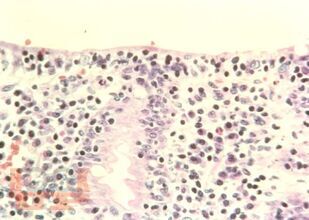

Учебное пособие посвящено актуальной проблеме педиатрии и детской гастроэнтерологии - синдрому мальабсорбции, который является причиной тяжелых осложнений, снижения качества жизни, инвалидизации детей при ряде тяжелых заболеваний. Рассмотрены методы общеклинического, лабораторного, инструментального обследования детей при синдроме мальабсорбции. Подробно описаны принципы оценки нутритивного статуса и выбора энтерального питания на фоне мальабсорбции. Особое внимание уделено особенностям патогенеза, клинического течения и терапии синдрома мальабсорбции на фоне распространенных тяжелых заболеваний, в частности, муковисцидоза, церебрального паралича, воспалительных заболеваний кишечника, пищевой аллергии, дисахаридазной недостаточности, целиакии.